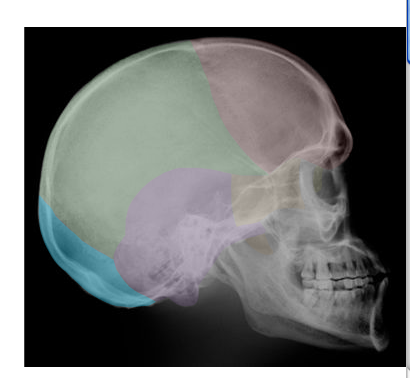

Cranial and Facial Bones

Students will use images and descriptions to reinforce their knowledge of the cranial and facial bones.

A | B |

in red,  | VOMER |

in orange,  | NASAL |

in blue,  | OCCIPITAL |

| SPHENOID |

in purple,  | TEMPORAL |

in green,  | PARIETAL |